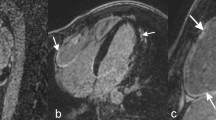

Two-dimensional illustration of bicuspid aortic valve during diastole (a) and systole (b) in a parasternal short axis view. Illustration of the pathological findings in suspected acute myocarditis confirmed later by CMR. Parasternal long axis view with increase ES-distance during early diastole (c), apical long axis view during diastole documenting increased LVEDV of about 265 ml (d), M-Mode-Sweep documenting increased end-diastolic LV diameter of 70 mm and increased ES-distance (e) and speckle tracking echocardiography of circumferential layer strain (f) documenting pathological regional strain of the anterior and lateral LV regions

In a second athlete BAV without any functional sequels was documented (Fig. 6a, b).

Relevant LV dilatation in the presence of increased LVRI, visually normal LV function and normal GLS was detected in one additional athlete (Fig. 6c–f). However, post-systolic shortening in the apical LV regions and abnormal rotational LV deformation with pathological circumferential strain values as well as pathological twist and untwisting was detected in this case as illustrated in the scheme of Fig. 3. The pathological LV function was also documented by a pathological increase of the early diastolic distance between septum and the anterior mitral leaflets, which would be the only suggesting finding in standard TTE. Due to echocardiographic findings suspected myocarditis was subsequently confirmed by a CMR. One athlete presented a mild aortic regurgitation.